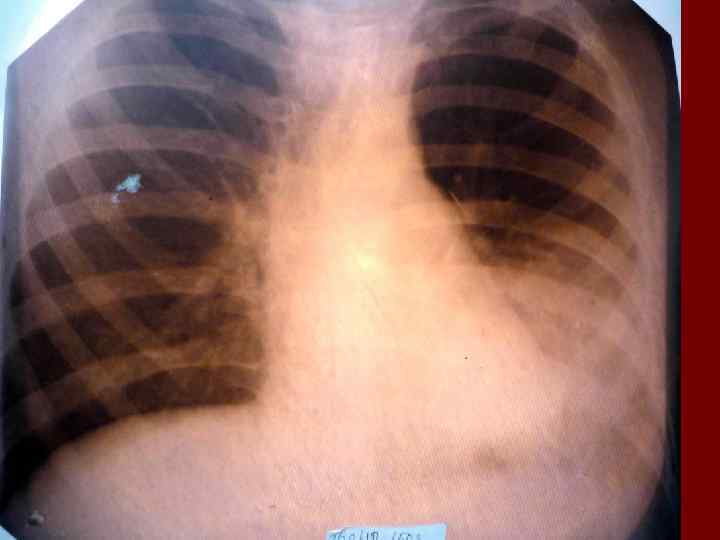

Долевая пневмония характеризуется лобарным пневмоническим инфильтратом. Крупозная ( пневмококковая) пневмония диагностируется прежде всего по клиническим данным. Крупозная пневмония сохраняет свою типичную картину пневмококковой пневмонии: острое начало с характерными клиническими данными, циклическое течение, несклонность к деструкции, гомогенной и лобарной инфильтративной тенью при рентгенологическом исследовании. Вместе с тем, широкое использование антибиотиков способствовало значительному снижению числа крупозных пневмоний у детей. Интерстициальная – редкая форма пневмоний, при которой оказывается поражен прежде всего интерстиций. Как правило, интерстициальная пневмония обусловлена вирусами, пневмоцистами, внутриклеточными микроорганизмами и грибами.

Морфологическую форму пневмонии определяют по клинико – рентгенологическим данным: выделяют очаговую, очагово – сливную, долевую ( крупозную), сегментарную и интерстициальную пневмонии. Очаговая – наиболее распространенная форма. Пневмонические очаги чаще бывают размером 1 см и более. Очагово – сливная – инфильтративные изменения в нескольких сегментах или во всей доле легкого, на фоне которых могут быть видны более плотные участки инфильтрации и/или полости деструкции. Сегментарная – в процесс вовлекается весь сегмент, который, как правило, находится в состоянии гиповентиляции, ателектаза. Морфологическая картина воспаления при очаговых и сегментарных пневмониях связана с первичным инфекционным воспалением в бронхах, что дает основание отнести эти варианты поражения легочной ткани к бронхопневмониям, нередко сопровождающихся бронхообструктивным или бронхообтурационным синдромами. В настоящее время данный тип пневмоний у детей встречается наиболее часто.